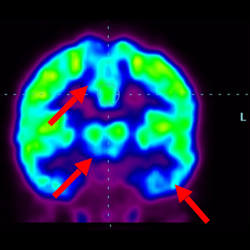

細胞治療前PET CT掃描顯示神經(jīng)組織中的藍/黑色區域,表明腦癱引起的大腦損傷。

細胞治療后,藍色和黑色區域減少,并且看到更活躍的區域。這表明損傷減少并改善了大腦功能。